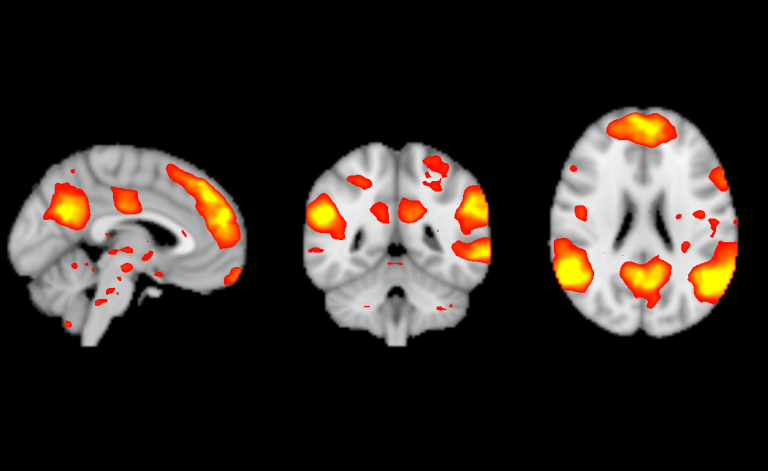

Imaging Capabilities With our brand-new General Electric 3.0 Tesla MRI Scanner, the suite is capable of performing a host of imaging analysis including the following: Site Menu Menu Icon of three lines stacked on top of eachother Sidebar Menu Chev Down Icon of hollow arrow pointing down Arrow Left Icon of arrow pointing left Neurotechnology Suite Chev Up Icon of hollow arrow pointing up Imaging Capabilities CONTACT Location: 50 Prescott Street (Gateway Park II) practicepoint@wpi.edu LinkedIn Icon of LinkedIn Logo